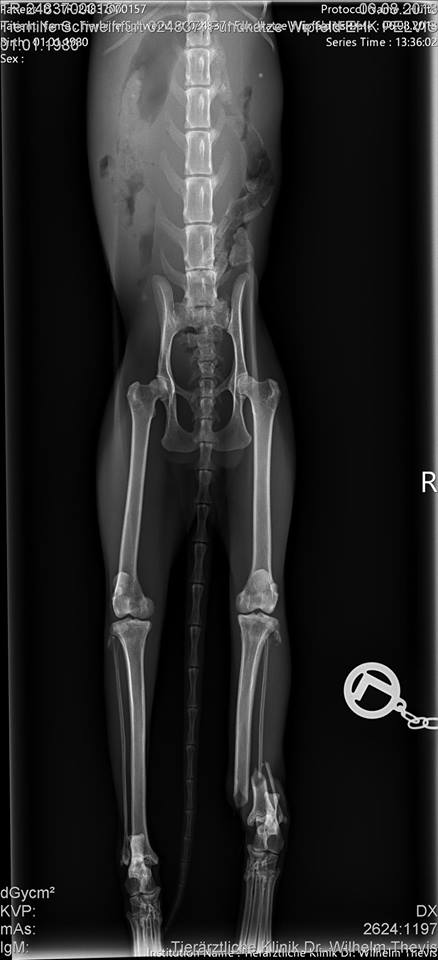

Vor Ort dann die Bestätigung: die arme Katze ist nur Haut und Knochen, zudem ist der Unterschenkel des linken Hinterlaufs eindeutig gebrochen. Sie zog das Bein in einer Schonhaltung hoch und der Fuß hing ohne Kontrolle herab.

Dort wurde durch eine Röntgen Aufnahme festgestellt, dass eine Operation unumgänglich ist. Also wurde Viola, wie wir sie getauft haben, am nächsten Tag gleich operiert, es wurden zwei Nägel in ihr Bein implantiert um die Fraktur zu stabilisieren.